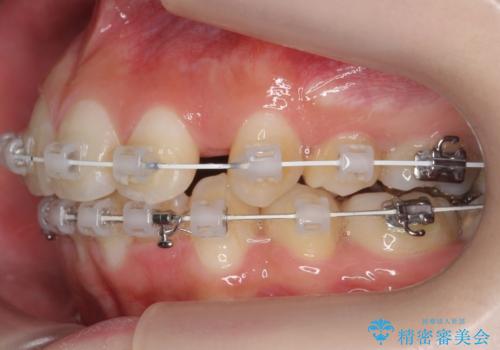

- ワイヤー矯正

- 3年1ヶ月

- 前歯のがたつきを主訴に来院。

顔が小さく、顎に大きな歯が入りきらない状態でした。

抜歯してワイヤー矯正を行いました。